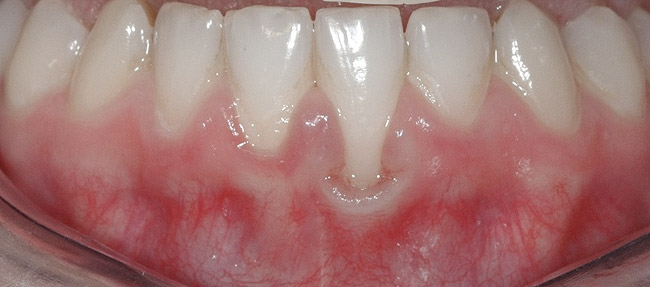

CASE 1 Fig 2. Pre-treatment clinical view of a 28-year-old patient with Miller Class I recession of the lower left central incisor treated with conservative SPT.

Figure 2

Fig 3. Two-year follow-up of same patient shows spontaneous root coverage.

Figure 3